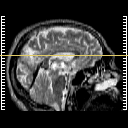

[Home][Help][Clinical] Slice 32

Click on sagittal image to select slice. Click on thin tickmark to change timepoint, or thick tickmark for overlay.